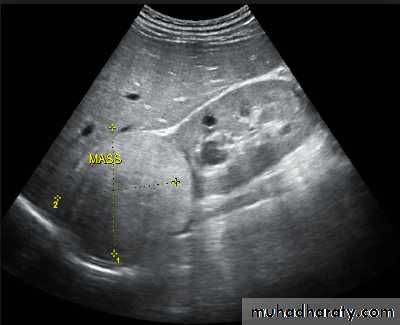

Ultrasound is typically ordered to exclude , stones , hydronephrosis or to evaluate renal size or suspected renal cysts .